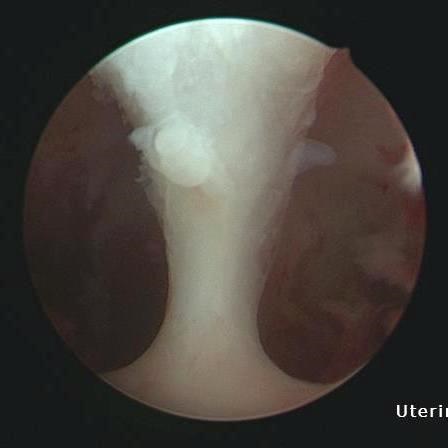

圖說:利用診斷性子宮鏡,李佩蓁醫師發現賴女士的子宮腔內有明顯間隔,確診為間隔子宮。